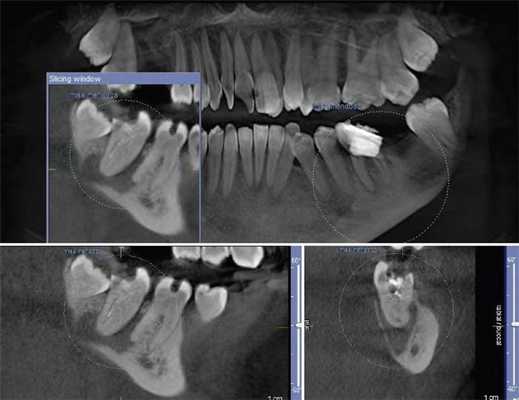

Сверхкомплектный зуб определен как парамоляр. Коронка парамоляра имела два бугорка и весьма сильно напоминала строение постоянного премоляра. Зуб повернут по оси, с расположением щечной поверхности дистально и мезиальной поверхности щечно. На мезиальной стороне парамоляра обнаружено кариозное поражение (Фото 2). Осмотр мягких тканей выявил воспаление пародонта между первым и вторым молярами и парамоляром. Сделаны рентгеновские снимки: панорамный, прицельный и окклюзионный. Чтение панорамного снимка было затруднено из-за небного расположения зуба. На прицельном и окклюзионных снимках обнаружено, что сверхкомплектный зуб поражен кариесом и имеет один корень (Фото 3 и 4).

Фото 3: Прицельный рентгеновский снимок, показывающий парамоляр с полностью сформованным зубом (указан стрелкой).

Фото 4: Окклюзионная рентгенограмма верхней челюсти, показывающая сверхкомплектный зуб (стрелка).

Наиболее ценным рентгенографическим исследованием является ОПГ с дополнительными прицельными снимками и снимками верхней и нижней челюсти в окклюзионной плоскости. Для четкой локализации непрорезавшегося зуба используют технику вертикального или горизонтального параллакса. Параллакс - это изменение обзора объекта на определенном фоне, основанное на перемещении обозревателя. Данная техника может быть осуществлена путем изготовления снимков одной зоны, но с разных углов двумя разными аппаратами. При использовании этого метода, как правило, точкой отсчета является корень примыкающего зуба. Вдобавок возможно использование конусно-лучевого КТ. Эта технология дает трехмерное изображение структур указанной зоны и является невероятно информативной при описываемой аномалии.